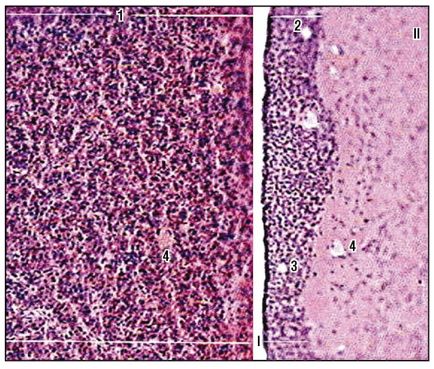

Fig. 164. Hipofiză (colorare cu hematoxilină și eozină, creștere mică): I - adenohipofiză: 1 - lobul anterior; 2 - zonă intermediară; 3 - pseudofollică; II - neurohidrofiză, lobul posterior: 4 - capilare sanguine